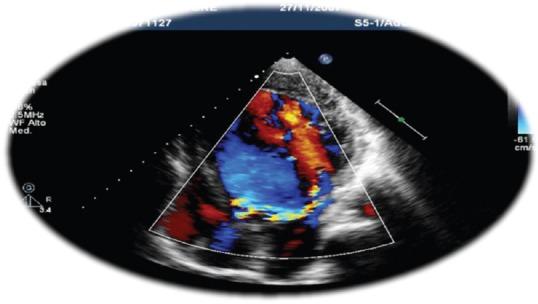

We present a case series of two adult patients with almost complete absence of the posterior mitral valve leaflet and who are asymptomatic or mildly symptomatic, with two different degrees of mitral regurgitation.

我们报告了一系列两个成年患者的病例,他们几乎完全没有二尖瓣后叶,且无症状或仅有轻微症状,伴有两种不同程度的二尖瓣反流。